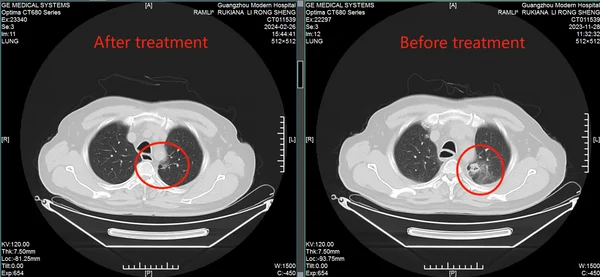

Результаты: от отчаяния к теннису

• Через 2 курса лечения: Кашель и одышка уменьшились, метастазы в легких и печени значительно сократились. • Через 6 месяцев: Плевральный выпот исчез, вес вернулся к норме. • Июнь 2024: Мохамад отдыхал на Бали и играл в теннис.

КТ-снимки подтвердили: опухоль в легком практически исчезла